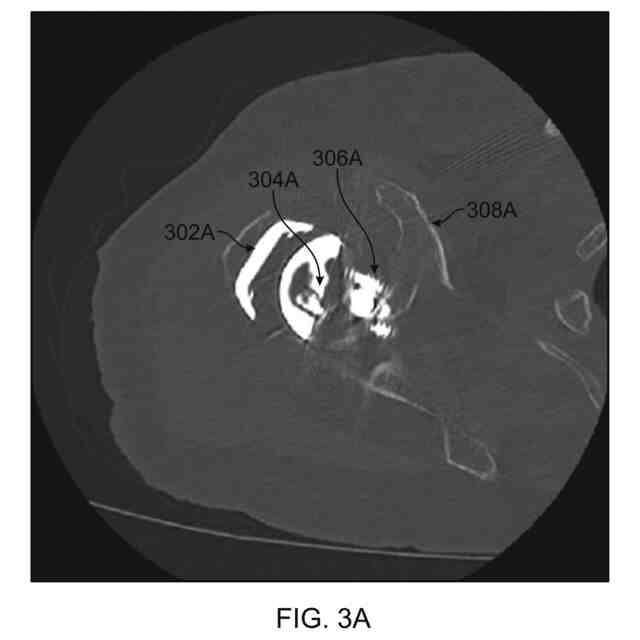

【課題】1つまたは複数のインプラントコンポーネントが留置されている整形外科的関節の骨埋め込み前の罹患した近似を決定するための技法について提供する。

【解決手段】システムは、患者の関節の画像データを取得し、関節が既存のインプラントを含むことを決定し、既存のインプラントに関するタイプの識別を生成することと関節の埋め込み前の罹患した近似を生成することの一方または両方を行うように構成される。

[0003]本開示は、1つまたは複数のインプラントコンポーネントが留置されている整形外科的関節の骨の埋め込み前の罹患した近似(pre-implant, morbid approximation)を決定するための技法について説明する。本開示は、整形外科的関節に埋め込まれるインプラントのタイプを決定する技法についても説明する。

[0004]一例によれば、方法は、罹患した解剖学的対象物のための形状モデルを決定することと、コンピューティングシステムによって、インプラントを含む患者の関節の画像データを取得することと、ここにおいて、画像データは、インプラントをもつ関節の3Dモデルを備える、インプラントをもつ関節の3Dモデルにおいて、骨に対応するボクセルを識別することと、骨に対応すると識別されたボクセルに基づいて、骨に対する初期形状推定を決定することと、アライメントされた初期形状推定を形成するように初期形状推定を形状モデルにアライメントすることと、骨の埋め込み前の罹患した近似を生成するために、アライメントされた初期形状推定に基づいて形状モデルを変形させることとを含む。